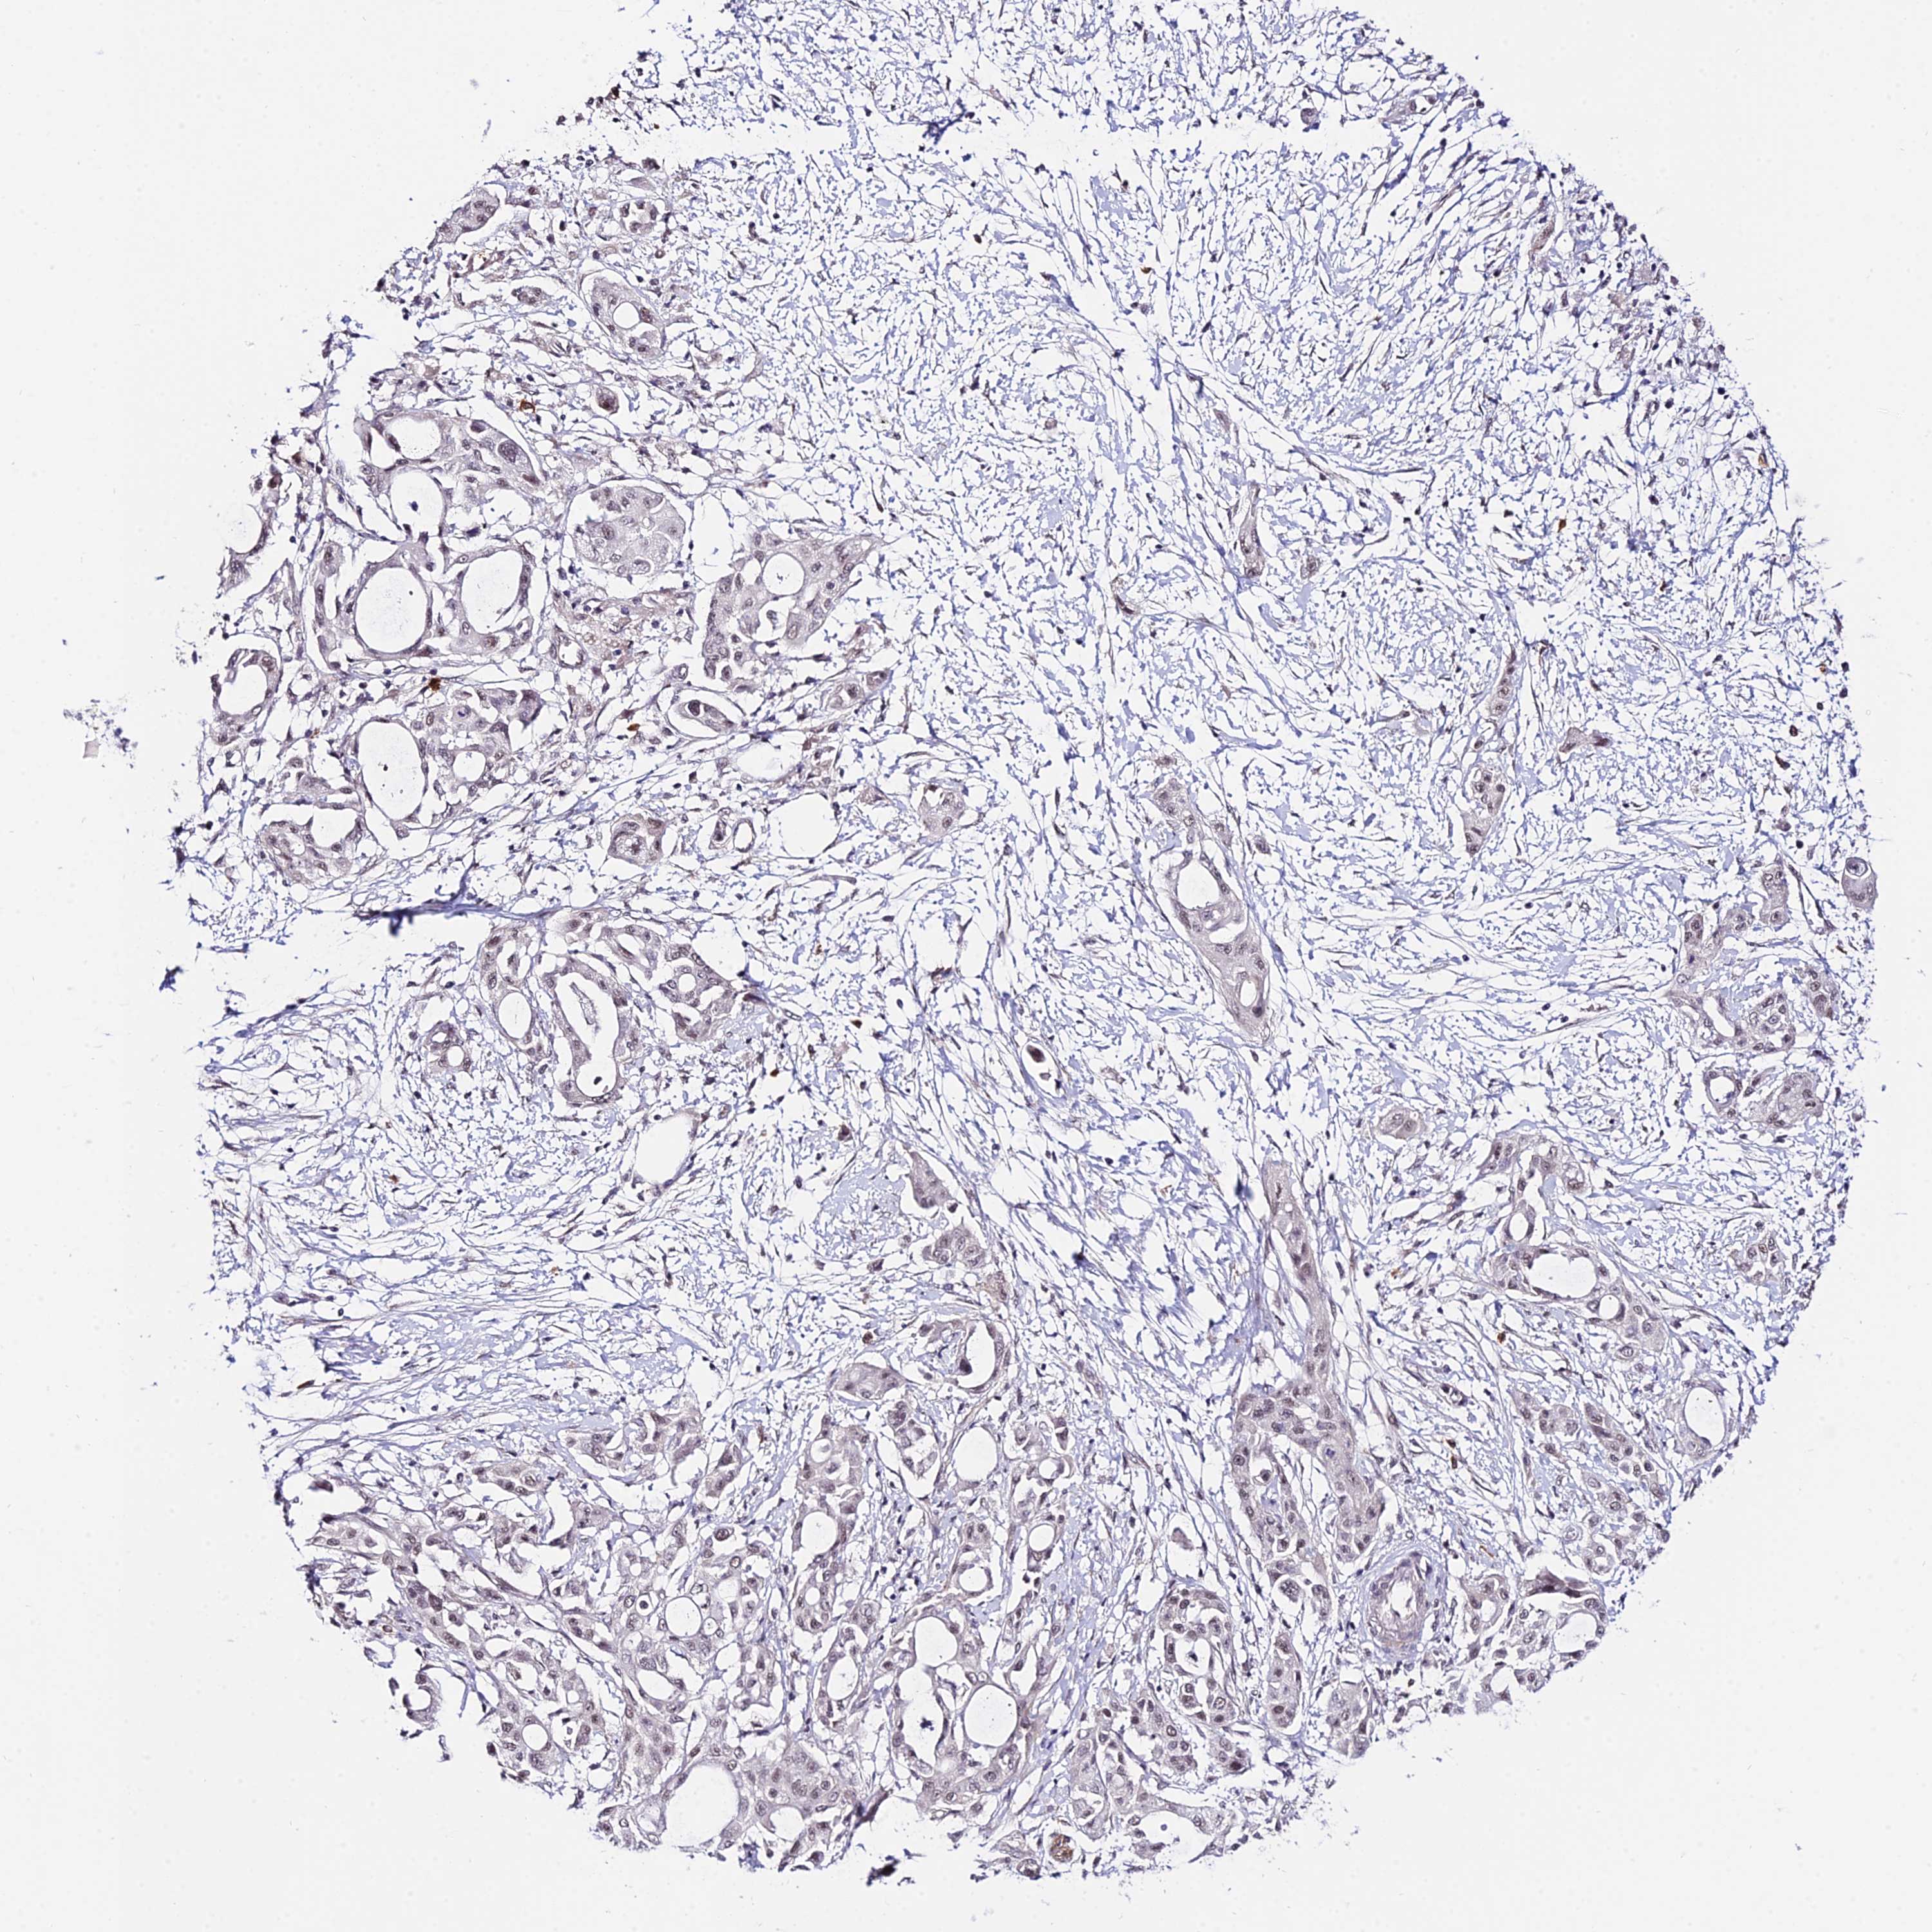

PANCREATIC CANCER - Protein expressioni

A mouse-over function shows sample information and annotation data. Click on an image to view it in a full screen mode. Samples can be filtered based on level of antibody staining by selecting one or several of the following categories: high, medium, low and not detected. The assay and annotation is described here.

Note that samples used for immunohistochemistry by the Human Protein Atlas do not correspond to samples in the TCGA dataset.

Antibody stainingi

Antibody staining in the annotated cell types in the current human tissue is reported as not detected, low, medium, or high, based on conventional immunohistochemistry profiling in selected tissues. This score is based on the combination of the staining intensity and fraction of stained cells.

Each image is clickable and will lead to virtual microscopy that enables deeper exploration of all samples and also displays staining intensity scores, fraction scores and subcellular localization as well as patient and tissue information for each sample.

Antibody HPA045156

Staining

High

Medium

Low

Not detected

Intensity

Strong

Moderate

Weak

Negative

Quantity

>75%

75%-25%

<25%

None

Location

Nuclear

Cytoplasmic/membranous

Cytoplasmic/membranous,nuclear

Adenocarcinoma, NOS